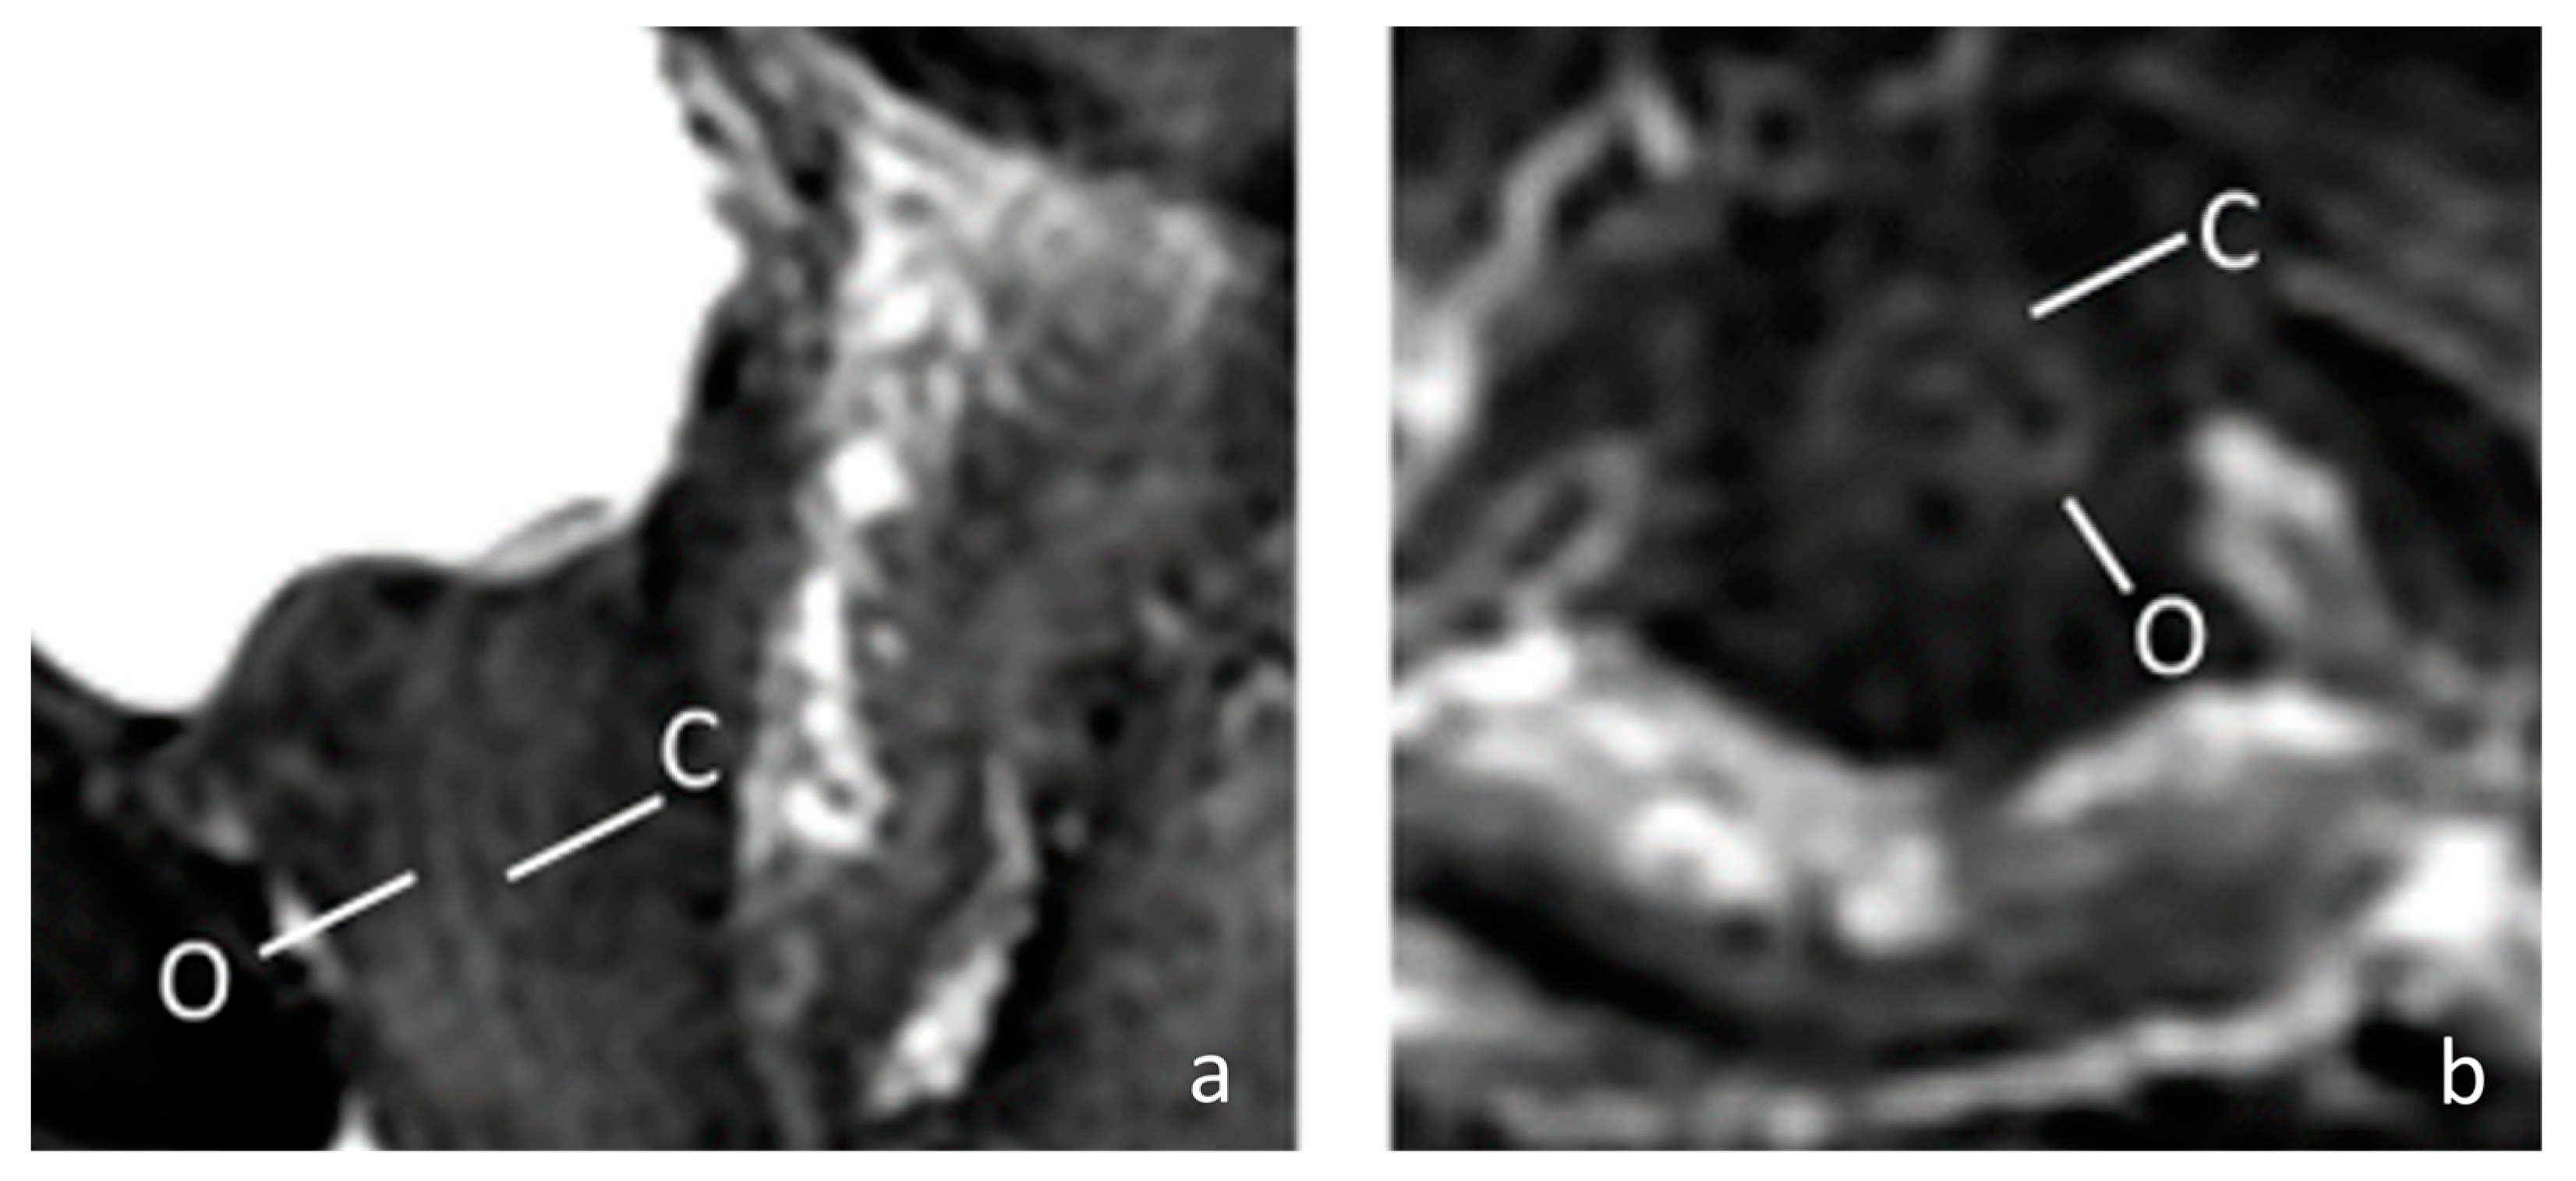

The female external sphincter is very thin, with a thickness of only about 2 mm with surrounding connective tissue [13,14]. Therefore, if a blind injection method is used, it is difficult to accurately achieve the correct position. In this study, we performed pelvis MRI to our patient to identify the structure of the female urethra more clearly. In this 67-year-old patient, the MRI showed a thin external sphincter with a thick connective tissue nearby in the mid urethra (Figure 2). Theoretically, the connective tissue adjacent to the sphincter can be reached using ultrasound positioning. Despite the fact that the goal is to be able to accurately inject into the external sphincter, as this layer of muscle is very thin, it is not easy to inject BoNT-A even with ultrasound guidance. Some of the medication may be in adjacent connective tissue, meaning it may reach the external sphincter through a diffusion mechanism of BoNT-A [21,22]. Previous studies have well documented that the striated urethral sphincter is thin and can be located at a distance outside the urethral lumen. However, clinical outcomes with the injection method have been inconsistent according to previous research. It is uncertain whether the injected botulinum toxin reaches the external sphincter as intended. Our study, which used transvaginal ultrasound, found that without proper guidance, the injected medication may deviate from the intended target. Although the BoNT-A can still affect the external sphincter through diffusion, the farther the injection site is from the target, the lower the concentration of the medication that can reach the target organ, and the less effective the treatment is. Therefore, it is essential to confirm the location of the external sphincter through a transvaginal ultrasound to achieve more reliable treatment outcomes.

Figure 2. The MRI image of a 67-year-old female urethra. (a) Sagittal fat-saturated T2-weighted of female urethra; (b) Axial fat-saturated T2-weighted of female urethra. The MRI shows a high signal intensity vascularized connective tissue (C) and low signal intensity outer muscular layer (O). (C = connective tissue; O = outer muscular layer).